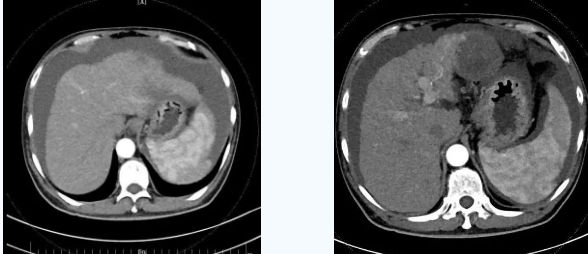

入院后,消化內(nèi)科五病區(qū)韓國宏院長帶領(lǐng)團(tuán)隊對患者做了深入的檢查,檢查后發(fā)現(xiàn)患者“肝硬化失代償期、頑固性腹水、原發(fā)性肝癌、慢性腎功能不全尿毒癥期、2型糖尿病、高血壓2級”等病癥,韓院長在對患者的病情進(jìn)行反復(fù)評估分析后表示,首先要明確患者目前腎透析后,仍然是大量腹水、無尿,那么腹水是肝源性的還是腎源性的,遂請多學(xué)科會診,結(jié)合相關(guān)檢查后明確,秦先生目前的大量腹水是由于門脈高壓導(dǎo)致的頑固性腹水,只有先解決門脈高壓導(dǎo)致的頑固性腹水,才可以繼續(xù)進(jìn)行癌癥治療,于是,韓院長決定為患者實施TIPS手術(shù)。

由于大量腹水、晚期肝癌加上尿毒癥等的綜合病癥,手術(shù)難度和危險系數(shù)都比平常增加了幾倍,面對這樣的情況,術(shù)前韓國宏院長帶著團(tuán)隊反復(fù)分析討論,全面評估,在患者的各項指標(biāo)達(dá)到手術(shù)標(biāo)準(zhǔn)后,對患者實施了經(jīng)頸靜脈肝內(nèi)門腔靜脈分流術(shù)(TIPS),手術(shù)取得成功,術(shù)后患者恢復(fù)良好。

術(shù)后一個月秦先生來院復(fù)查,腹水已明顯較前減少,精神和飲食較術(shù)前明顯好轉(zhuǎn)。

韓國宏院長介紹,TIPS原理是采用特殊的介入治療器械,在X線透視導(dǎo)引下,經(jīng)頸靜脈入路,建立肝內(nèi)的位于肝靜脈及門靜脈主要分支之間的人工分流通道,并以金屬覆膜內(nèi)支架維持其永久性通暢,達(dá)到降低門脈高壓后減少腹水產(chǎn)生,控制和預(yù)防食道胃底靜脈曲張破裂出血的目的。